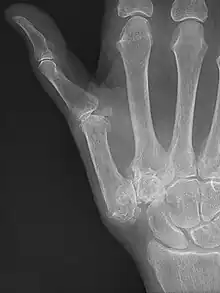

TMC OA is diagnosed based on symptoms and signs.[8] Radiographs can confirm the diagnosis and the severity of TMC OA. Other diagnoses in this region include scaphotrapezial trapezoid arthritis and first dorsal compartment tendinopathy (De Quervain syndrome) although these are usually easy to distinguish.

TMC OA severity was classified by Eaton and Littler which can be simplified as follows:[21][22]

Stage 1:

- slight widening of the joint space

- < 1/3 subluxation of the joint (in any projection)

Stage 2:

- Osteophytes, < 2 mm in diameter, are present. (usually adjacent to the volar or dorsal facets of the trapezium)

Stage 3:

- Osteophytes, > 2 mm in diameter, are present (usually adjacent to the volar and dorsal facets of the trapezium)

- Slight joint space narrowing

Stage 4:

- Narrow joint space

- Concomitant scaphotrapezial arthritis

A simpler classification is no arthritis, some arthritis, and severe arthritis.[23] This simpler classification system omits the potentially contradictory details of the Eaton/Littler classification and keeps scaphotrapezial arthrosis separate.